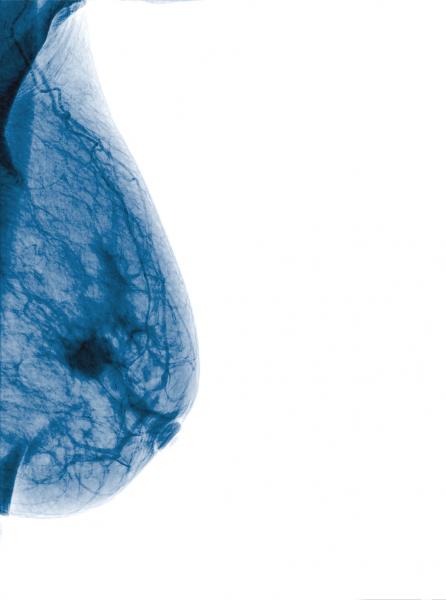

Women prefer to get their mammograms every year, instead of every two years, according to a new study presented at the annual meeting of the Radiological Society of North America (RSNA), Nov. 26-Dec. 1 in Chicago.

The U.S. Food and Drug Administration (FDA) issued an approval letter for the Planmed Clarity 2-D full-field digital mammography (FFDM) system on Dec. 28, 2017, the company announced. The Planmed Clarity 2-D system is a digital mammography system that provides high image quality, optimal ergonomics and excellent usability for breast cancer screenings, according to the company. In addition to screening mammograms, the system supports diagnostic work-up examinations and biopsy procedures.

Despite decades of progress in breast imaging, one challenge continues to test even the most skilled radiologists ...

Women with higher body mass index (BMI) face an increased risk of not detecting their breast tumor until it has become large, according to a study presented at the 2017 annual meeting of the Radiological Society of North America (RSNA) in Chicago in November. Researchers said the findings suggest that women with higher BMI may need shorter intervals between mammography screening exams.

Sixty million women undergo regular screening mammography in the United States, but even in the digital age, it is ...